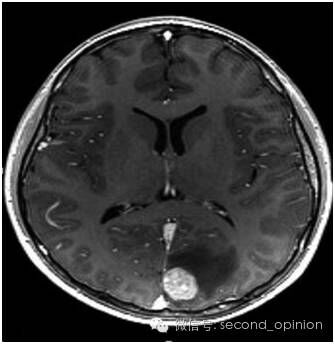

脑转移瘤治疗前3cm

脑转移瘤治疗后基本消失